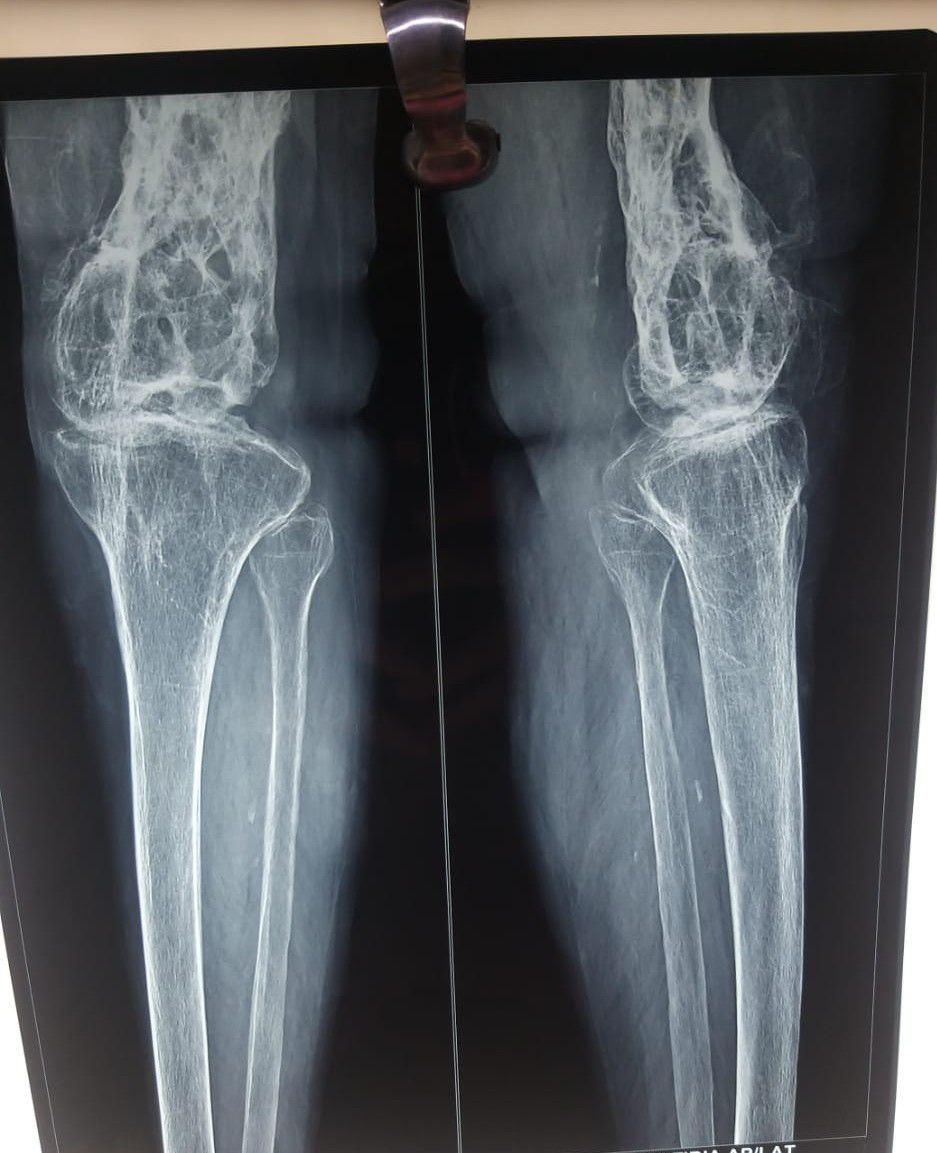

what's the disease diagnosis?

Diagnosis : Osteomyelitis